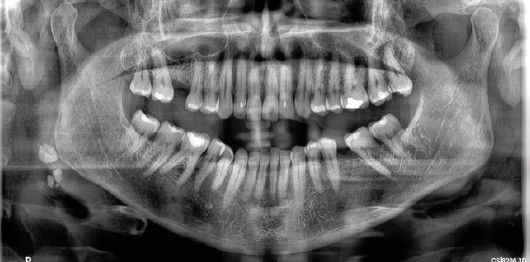

Paciente 3

Se presenta a un paciente de 64 años, con periodontitis estadio IV generalizado grado B. Ha sido tratado periodontalmente y se encuentra en mantenimiento periodontal desde hace 20 años. Entre sus antecedentes médicos cabe destacar que padeció hepatitis C, sin tratamiento actual, y que presenta actualmente espondilitis anquilosante sin tratamiento médico, salvo antiinflamatorios no esteroideos en momentos de dolor articular e hipertensión arterial medicada con ramipril y controlada. En su cita de mantenimiento, se le realiza una radiografía panorámica de control y se observan 2 imágenes calcificadas rectangulares de aproximadamente 5 mm en zonas blandas del cuello en el lado derecho, junto con otras imágenes puntiformes más pequeñas en la zona más interna, aproximadamente a 3-4 centímetros del ángulo mandibular (Figuras 6, 7). Ante la sospecha de que fueran calcificaciones carotídeas, fue remitido a su médico de atención primaria para que valorase la necesidad de realizar un diagnóstico específico. El especialista en cirugía vascular le solicitó eco-Doppler, en el que fue confirmada una placa de ateroma de predominio cálcico, situada en la bifurcación carotídea derecha, con unas dimensiones de 5 por 1,5 mm aproximadamente, que no producía estenosis hemodinámicamente significativa. Se le solicitó además analítica, en la que no se observaron alteraciones significativas.

En este paciente, como en la primera, el diagnóstico de ateromas carotídeos se realizó también de manera previa a la existencia de síntomas y de estenosis carotídea, hecho fundamental a la hora de evitar eventos cerebrovasculares.

Cuando son pequeñas tienen una apariencia radiográfica circular. Sin embargo, los grandes ateromas tienen forma lineal o rectangular delgada. En el paciente 1, las calcificaciones eran bilaterales, grandes, rectangulares, irregulares, situadas entre 1-2 cm posteroinferiores al ángulo mandibular, suprayacentes a los tejidos blandos prevertebrales. En el paciente 2, sin embargo, las calcificaciones aparecían unilateralmente, más pequeñas, circulares y múltiples, suprayacentes a los tejidos blandos prevertebrales y adyacentes al hioides.

En el paciente 1 y 3 las calcificaciones aparecían en la bifurcación carotídea, el lugar más frecuente de aparición, según Friedlander y Friedlander8. En los pacientes 2 y 3 los ateromas carotídeos eran unilaterales, izquierdo en el paciente 2 y derecho en el paciente 3, coincidentes con las imágenes calcificadas de manera unilateral que se habían observado en la radiografía panorámica solicitada únicamente por motivos de control periodontal.